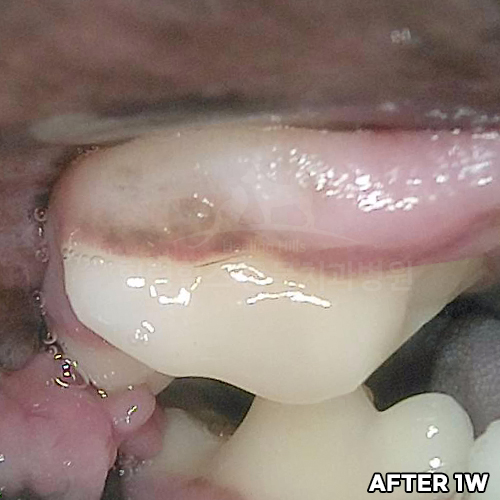

강아지잇몸에혹! Ossifying fibromatous epulis (골화성 섬유종성 치은종)! 강아지치은종 수술 전 후 모습 - 힐링힐스동물치과병원 -

2025.09.04